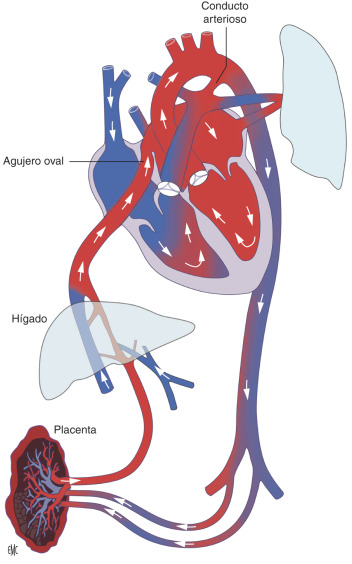

Trayecto de la sangre en la circulación fetal

La sangre parte desde la placenta, donde se efectúan todos los cambios nutritivos con la sangre de la madre. Desde allí la sangre oxigenada transcurre por la vena umbilical, hacia el feto.

El trayecto de sangre proveniente de la vena umbilical, se dirige hacia el hígado fetal y a través del conducto venoso, llega a la vena cava inferior.

En el hígado hay un aporte de sangre venosa proveniente de la vena porta hepática . Desde este punto, los vasos sanguíneos contienen sangre mezclada

A la vena cava inferior se incorpora también sangre venosa de los miembros inferiores y de la parte infradiafragmática del tronco, la cual en conjunto penetra en el atrio derecho, donde se mezcla con la sangre venosa que procede de la cabeza y de los miembros superiores, a través de la vena cava superior y sangre proveniente de las paredes del corazón a través del seno coronario.

Desde la aurícula derecha parten dos corrientes:

- La circulación mayor atraviesa el tabique interatrial por el foramen oval (de Botal), recorre el atrio (aurícula) y el ventrículo izquierdo para pasar a la aorta, que la distribuye en el resto del cuerpo. Es la corriente principal.

- La circulación menor pasa al ventrículo derecho y llega a los pulmones por el tronco pulmonar.

Debido a que los pulmones del feto no son funcionales, no se modifican la composición gaseosa de la sangre, la cual regresa al atrio izquierdo por las venas pulmonares y se vierte a la circulación aórtica.

A partir del sistema aórtico, por medio de las arterias umbilicales, la sangre es enviada de nuevo a la placenta.

La circulación mayor proveniente de la aorta, irriga el cuerpo del feto con sangre arterial y venosa mezcladas, cuyo objetivo es la nutrición de los tejidos para favorecer el crecimiento.

En el embrión o feto, no existe ninguna “circulación funcional” en su sistema digestivo ni en las glándulas de secreción externa, riñones o piel. Solo el hígado recibe sangre oxigenada proveniente de la madre a través de la vena umbilical.